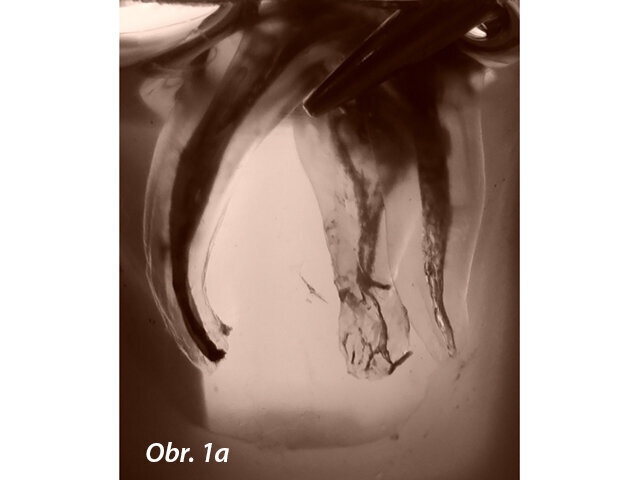

Úspěšné endodontické ošetření závisí na řadě faktorů, včetně správné instrumentace, úspěšné irigace a dekontaminace systému kořenových kanálků včetně apikálního zakončení a špatně přístupných oblastí jako jsou zúžení a postranní a vedlejší kanálky (obr. 1a, 1b).